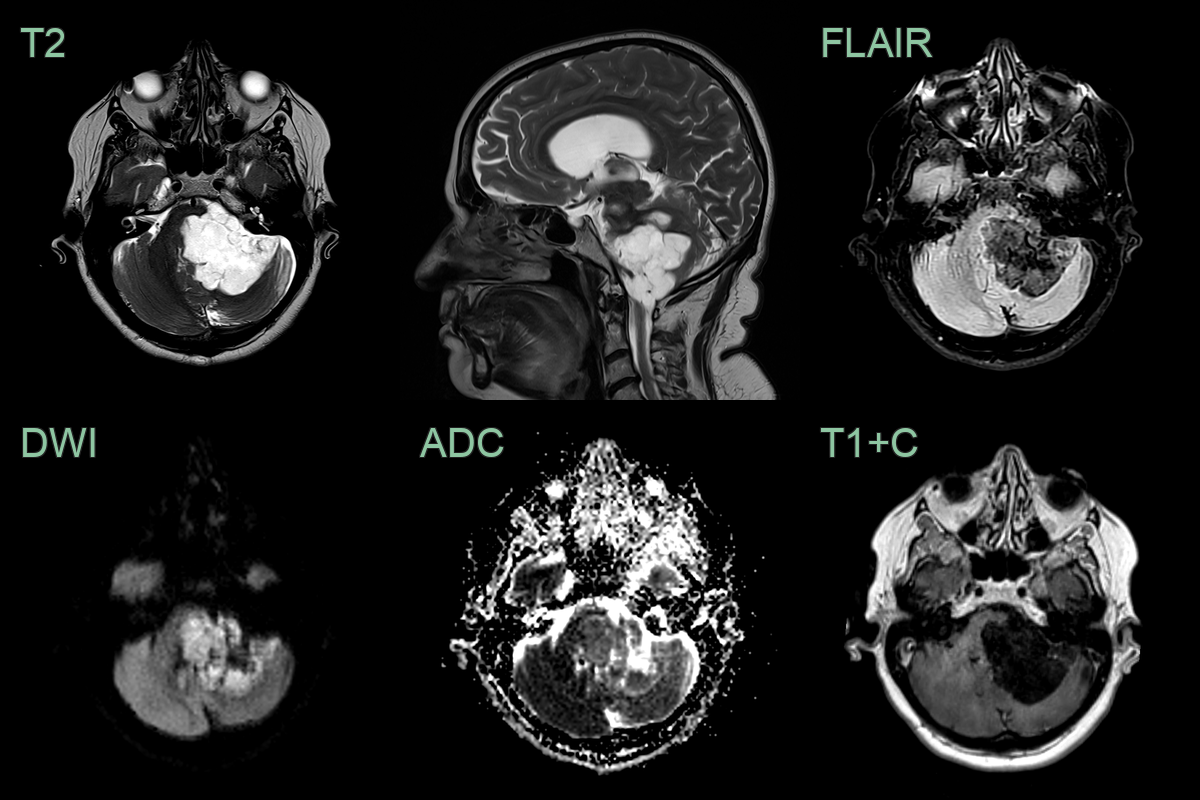

- MRI:

- T1: Hypointense to isointense

- T2: Hyperintense

- FLAIR: Heterogeneous signal intensity

- DWI: Marked restriction (key diagnostic feature)

- No enhancement with gadolinium

- "Popcorn" appearance on DWI due to lamellated keratin

- 60-year-old patient present with ataxia and poor left-sided hearing.

- MRI showed a T2-hyperintense non-enhancing lobulated lesion with low ADC values in the left side of the posterior fossa, encasing the 7th and 8th nerve complexes.

- There was significant mass effect on the cerebellum (presumably relevant to the ataxia) but there was no oedema, indicating that this lesion has grown slowly.